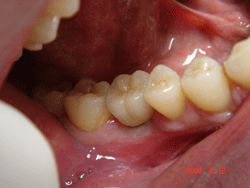

| <症例4> |

| 右下6番パーフォレーションによる骨吸収のため抜歯。両隣在歯がノンカリエスのためインプラントを選択。 |